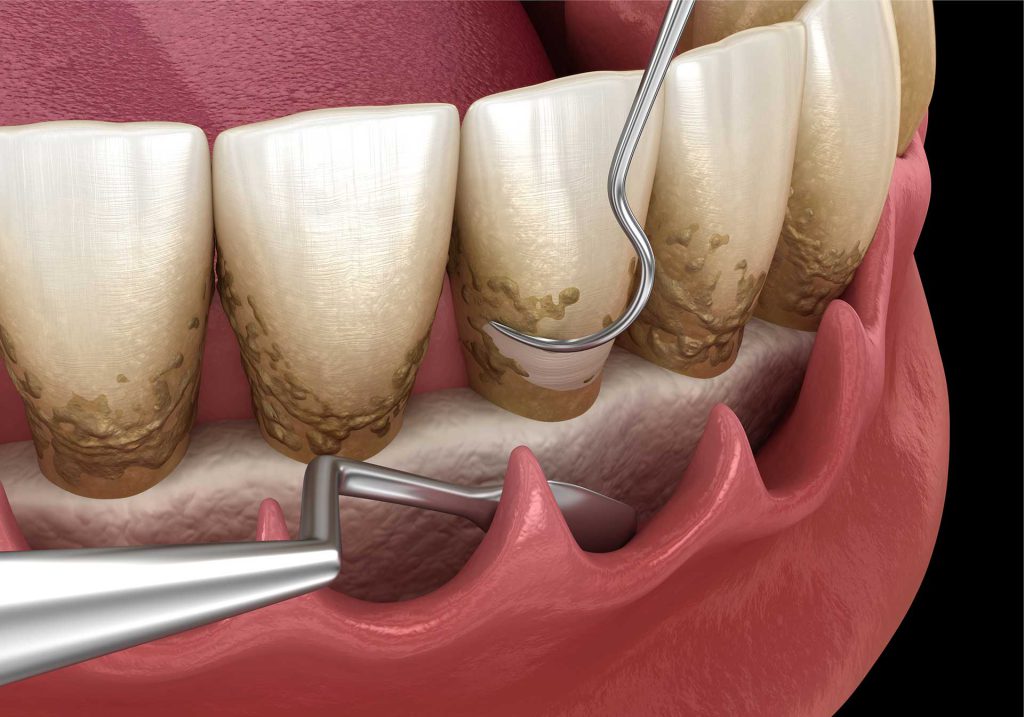

جرم گیری عمیق دندان چیست؟

جرم گیری عمیق دندان برای زمان هایی است که لثه دچار بیماری و عفونت باشد. این کار با هدف تمیز کردن زیر لثه و ریشه دندان صورت می گیرد و یک روش غیرجراحی موثر برای درمان بیمای لثه به حساب می آید. برای این کار، نواحی تحت درمان را به صورت موضعی بی حس می شوند، سپس با یکی از ابزارهای جرم گیری، پلاک های مضر برداشته می شوند. در مرحله بعدی بافت لثه به عقب رانده می شود و فرایند روت پلنینگ یا تمیز کردن ریشه انجام خواهد شد. تجربه خونریزی بین 1 تا 2 روز بعد از این کار طبیعی است و باید با شستشوی دهان با محلول آب نمک و دهانشویه، عوارض این مدل جرم گیری را مهار کرد.